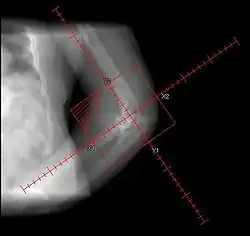

• Randomized. 161 patients. Preop RT 7/1 (<4 hours) vs. Postop RT 17.5/5 (<=96 hours). Portals periacetabular and intertrochanteric soft tissues

• Failure rate: radiological overall 11%; preop 19% vs. postop 5% (SS). Functional 14% Highest failure in pre-op RT for Brooker Grade III-IV (39%), otherwise preo-op and post-op outcomes comparable

• Randomized, multi-institutional. 98/122 patients with risk factors, following elective hip replacement. Treated with pre-op RT 7-8/1 <4 hours vs. post-op RT 7-8/1 <48 hours. Fields to soft tissues between periacetabular region of pelvis and intertrochanteric portion of femur. Median F/U 9.5 months

• Failure rate: radiographic preop 26% vs. postop 28% (NS); clinical 2% vs. 5% (NS)